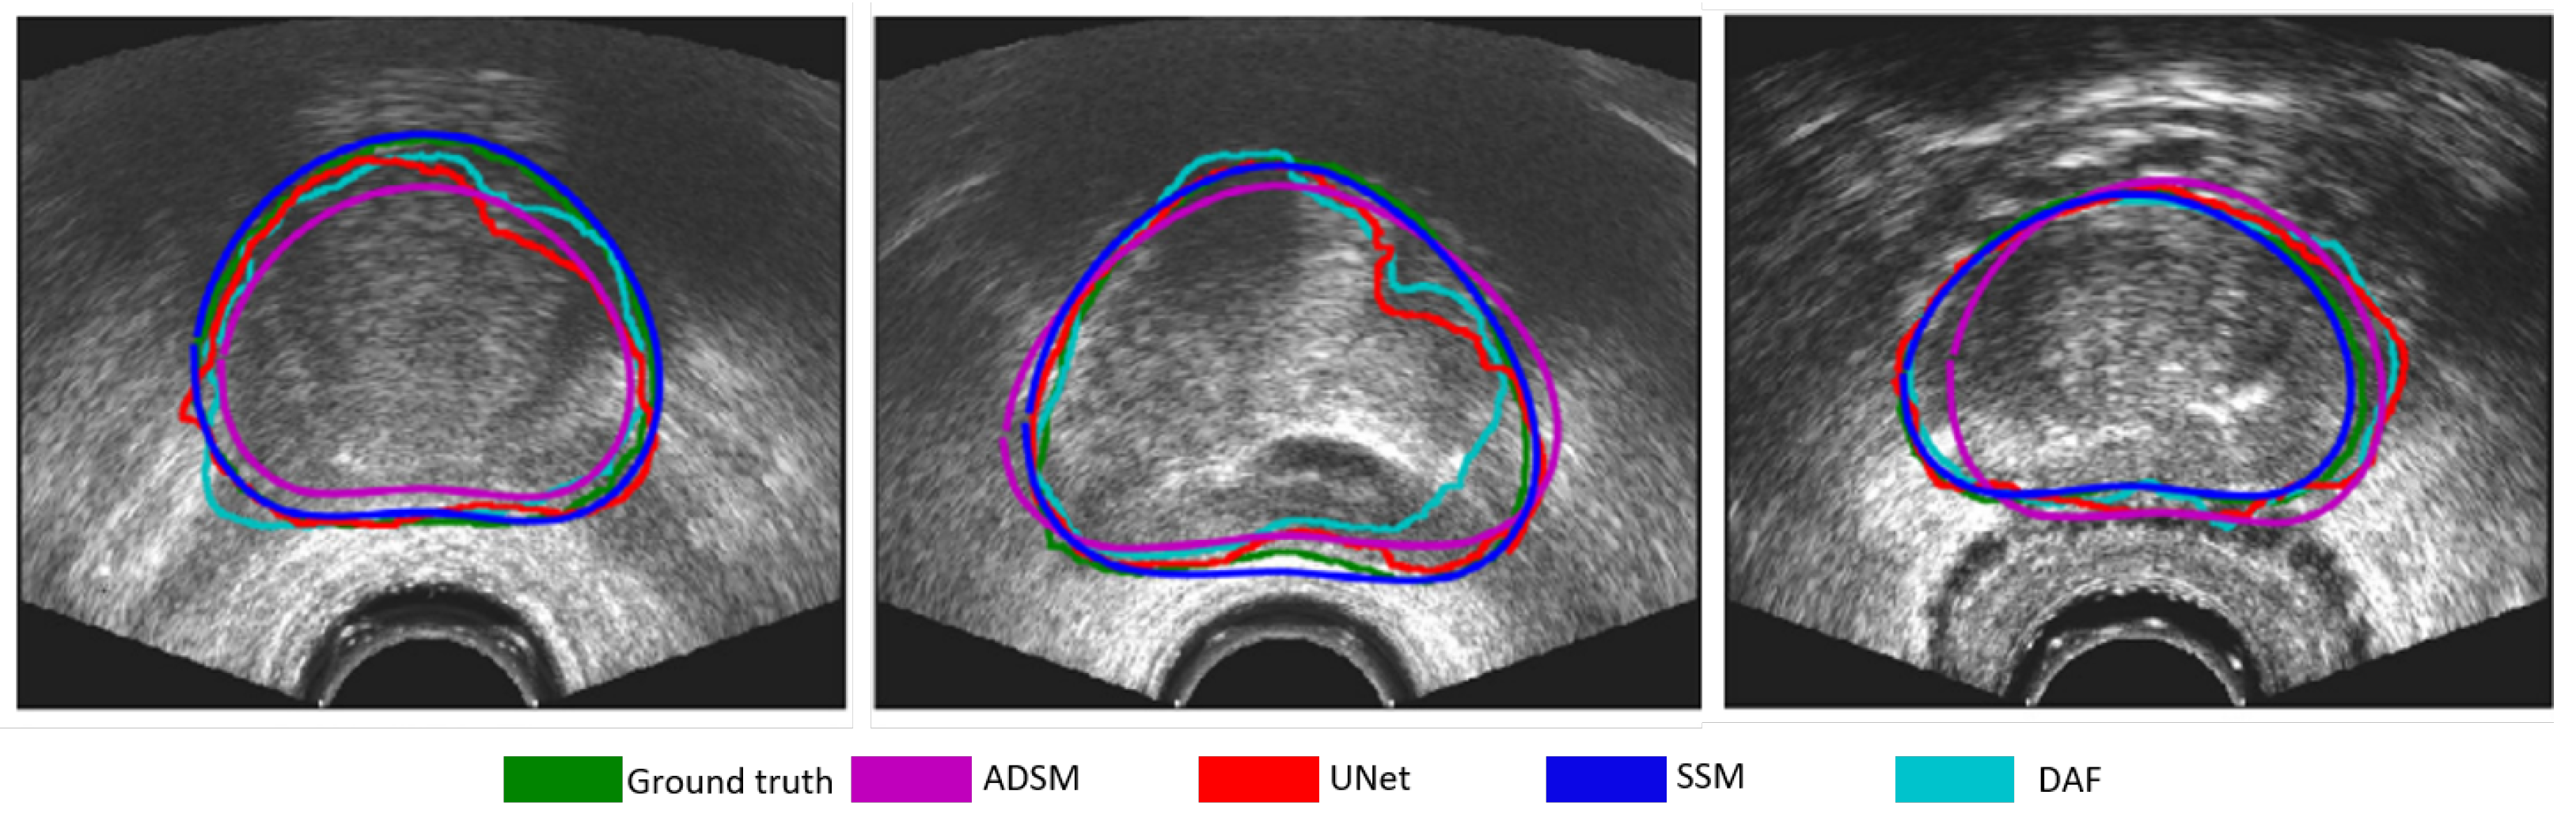

- Wang, Y.; Ni, D.; Dou, H.; Hu, X.; Zhu, L.; Yang, X.; Xu, M.; Qin, J.; Heng, P.A.; Wang, T. Deep Attentive Features for Prostate Segmentation in 3D Transrectal Ultrasound. IEEE Trans. Med. Imaging 2019, 38, 2768–2778. [Google Scholar] [CrossRef] [PubMed]

| Wang et al. (2019) [37] | Modified U-Net in which spatial attention is integrated. |